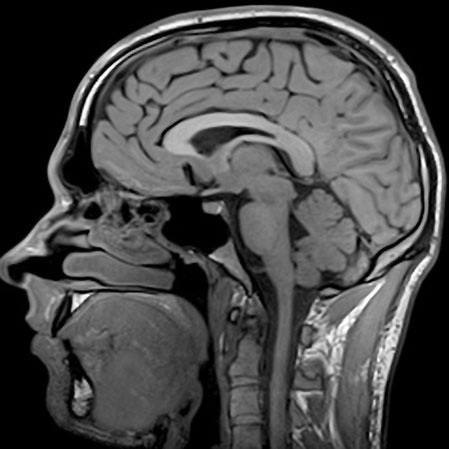

7.7. Как работает МРТ?

Современная медицина уже никого не удивляет тем, что может увидеть человека насквозь. Но вы только представьте, сколько различных методов изобретено: УЗИ, рентген, МРТ. Пожалуй, самым совершенным является последний, о нем и поговорим. МРТ позволяет создавать трехмерное изображение внутренностей человека чуть ли не в полный рост, при этом никакого вредного воздействия не оказывает! Так каков его принцип действия?

Иллюстрация к книге — Чердак. Только физика, только хардкор [i_100.jpg]

Принцип действия

Магнитно-резонансный томограф представляет из себя огромный магнит, с очень сильным полем. В самых сильных моделях оно может быть в 100 000 раз больше магнитного поля Земли! Так вот, ядра наших атомов сами являются маленькими магнитиками (потому что у них есть спин, они как бы вращаются и как бы являются малюсенькими электротоками, ведущими себя, как электромагнит). Соответственно они могут взаимодействовать с внешним магнитным полем и поворачиваются либо вдоль поля, либо против. Следует отметить, что так ведут себя только ядра с нечетным количеством протонов и нейтронов. Но все МРТ настроены на повороты ядер водорода, который содержится в большом количестве в организме в составе воды и других соединений.

Если облучить ядро электромагнитной волной определенной частоты, то оно может поглотить ее энергию и повернуться на 90 или 180 градусов, в зависимости от частоты. Через некоторое время ядро релаксирует в свое исходное состояние и излишек энергии излучает в виде электромагнитной волны. Это излучение принимается антеннами по сути как обычное радио, и если облучать ткани, то по интенсивности «отклика» можно понять, много там ядер водорода или нет. В разных тканях его разное количество, поэтому на изображении отчетливо видна разница между ними.

Но все же это достаточно дорогой и технически сложный способ наблюдения за внутренностями человека. Дело в том, что частота поглощения зависит от поля. Если бы везде поле было одинаковым, то поглощение и излучение происходило бы везде, мы бы не узнали, откуда пришел сигнал, и картинки не получилось бы.

Поэтому на практике делают так. Включают основной магнит, радиоизлучатель и так называемые градиентные поля. Они добавляются или вычитаются из поля основного магнита, делая его неоднородным. Из-за этого резонансное поглощение энергии происходит не везде, а только в маленьком участочке. Оттуда летят радиоволны и уже принимаются антеннами. Изменяя градиентные поля, мы передвигаем место резонанса, как бы сканируя тело, и получаем некий «отклик» из каждой точки тела.

В разных тканях содержится разное количество водорода (в воде и других соединениях), поэтому мы получаем разный отклик и можем восстановить картину внутренних органов. Так же время релаксации тоже различно для разных тканей! Во многих исследованиях измеряют и его, получая очень точную картину.